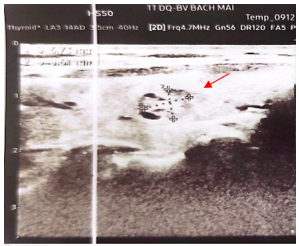

- Siêu âm tuyến vú: Hình ảnh các nốt giảm âm 1/4 trên ngoài vú phải, lớn nhất kích thước 8x12,9mm, bờ thùy múi, có xu hướng lan theo ống tuyến kèm theo có thành phần nang bên trong.

Hình 2: Hình ảnh siêu âm tuyến vú: Hình ảnh nốt giảm âm 1/4 trên ngoài vú phải (BIRADS 4) (mũi tên màu đỏ).